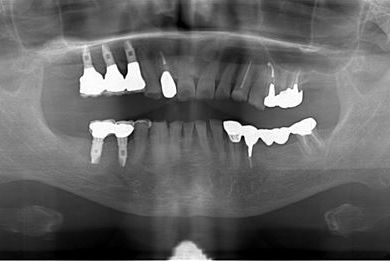

インプラントの症例写真 IMPLANT

骨再生インプラント治療+セラミック治療

| 性別/年齢 | 男性 / 60歳 | ||||||||||||||||||||||||||||||||

| 主訴 | 右上奥歯が動いて痛みがある。 | ||||||||||||||||||||||||||||||||

| 治療方針 | サイナスリフトにて上顎洞を拳上し、骨再生療法を用いてインプラント治療を可能にする。 | ||||||||||||||||||||||||||||||||

| 治療内容 | インプラント5本(サイナスリフト、GBR)、ハイブリッドセラミッククラウン5本、メタルボンドセラミッククラウン1本(メタルボンド用土台1本)、ハイブリッドセラミックインレー、遊離歯肉移植手術 | ||||||||||||||||||||||||||||||||

| 治療期間 | 1年7ヶ月 |